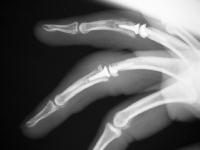

These are before and after radiographs of middle and ring proximal interphalangeal joints in a young man after a rotating blade injury resulting in dorsal bone and soft tissue loss. Initially treated elsewhere with K wire fixation, ring finger skin graft and abdominal flap reconstruction of the middle finger, he presented with instability, stiffness, pain and lateral angulation. Surgery was technically difficult because normal landmarks were distorted or missig. Despite complex bone and soft tissue loss,  stability was rendered in part by the restoration of concentric joint surfaces.

Anteroposterior views:

Click for larger image